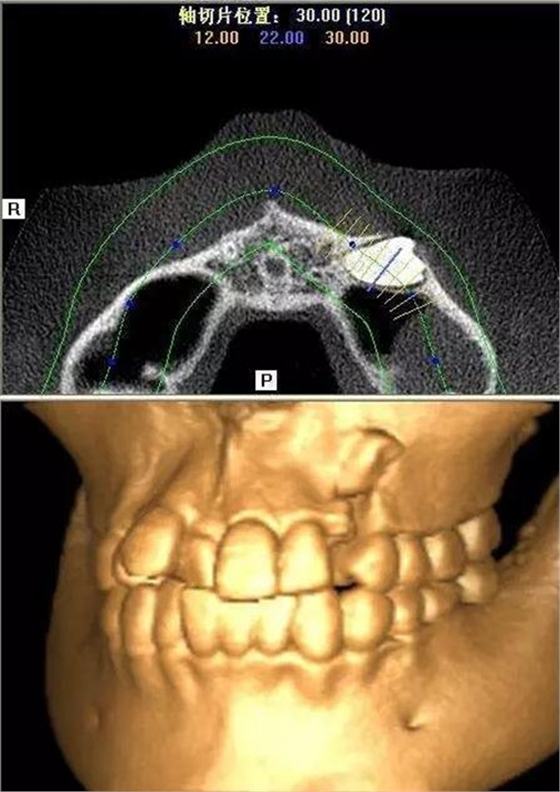

本案:患兒,女,14歲,因牙齒矯正來院,檢查見83滯留,43未見萌出,拍片發(fā)現(xiàn):43埋伏阻生于31、41、42根尖下方,按照正畸診療計劃,擬行43拔除術。

CBCT顯示